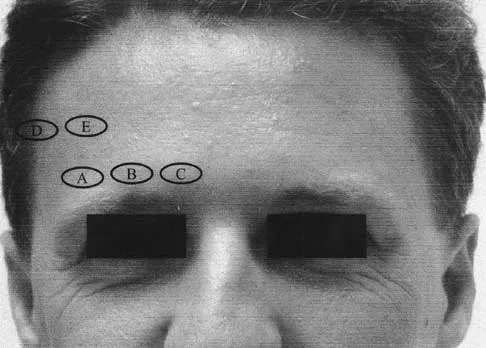

Figure 15 shows possible locations of anterior pin sites for halo fixation. What location is considered most ideal?